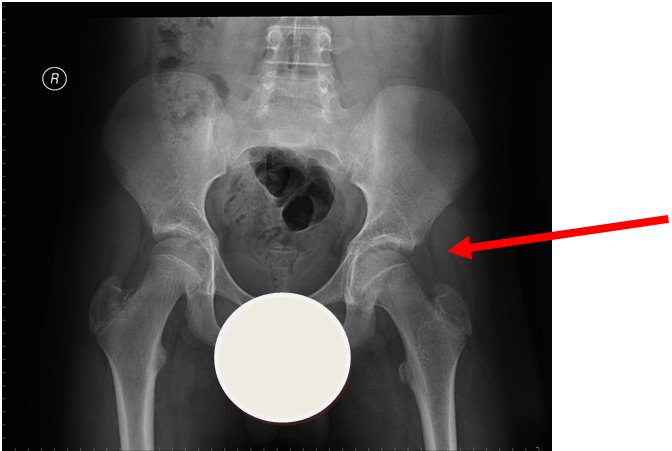

4. Slipped Upper Femoral Epiphysis (SUFE)

More obvious left sided SUFE (AP)

Case courtesy of Dr Gagandeep Singh, Radiopaedia.org. From the case rID: 7228

Usually occurs in late childhood / adolescence and is more common in boys than girls (2:1).  It also presents more commonly in children whose weight is above the 90th centile.  Bilateral in 25% of cases.  Onset can be acute or subacute (ie children may present with >1day h/o pain or limp).  Children may walk with an antalgic gait out-toeing, with shortening of the affected limb.  If the slip is acute, the child may be unable to walk.  Diagnosis is made radiologically and frog-lateral views are required as it may be missed on AP views.  Urgent orthopaedic opinion is required.  Unstable slips can lead to avascular necrosis of the femoral head.

Investigation

• X-ray - AP pelvis with frog lateral view (must be discussed with ortho 1st on call / ED consultant if child <8 years old)